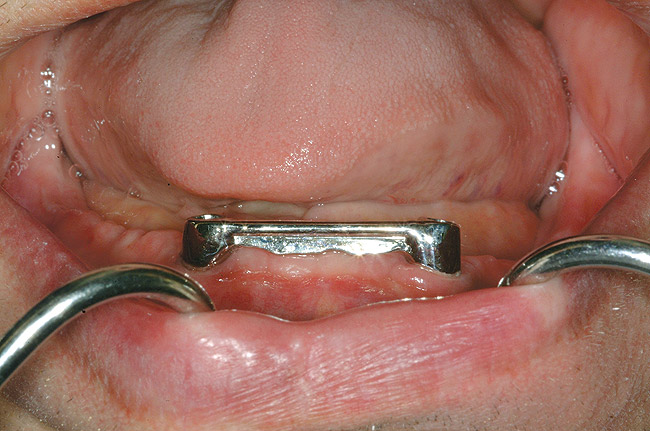

Figure 4  An example of a two-implant tissue bar for an implant-assisted prosthesis.

Figure 4

When dental implants were introduced by Brånemark, they were intended primarily for the completely edentulous patient, specifically the edentulous mandible. The initial prosthesis was a fixed restoration commonly referred to as a fixed bone anchored bridge. That particular prosthetic design is now the fixed-detachable hybrid prosthesis and has been highly successful for both the implants and prostheses.12,13 Implants have also been used for overdenture restorations14 and can be implant-assisted or implant-supported. With implant-assisted prostheses, the implants and mucoperiosteum share the forces of occlusion. A simple two-implant overdenture, either a Hader Bar® (Sterngold™, Attleboro, MA) or Locator® abutment (Zest Anchors, Escondido, CA), are examples of implant-assisted overlay prostheses and are always a removable restoration (Figure 4 and Figure 5). With implant-supported prostheses, the forces of occlusion are borne solely by the implants. This prosthesis can be an overlay prosthesis or a fixed restoration. Milled bar restorations, overdentures with bar substructures, and metal ceramic restorations attached to implant abutments by either screws or cement are examples of implant-supported restorations. One of the primary benefits of using dental implants in edentulous patients is the preservation of the residual bone, which will provide a better opportunity for future successful prosthetic restorations.